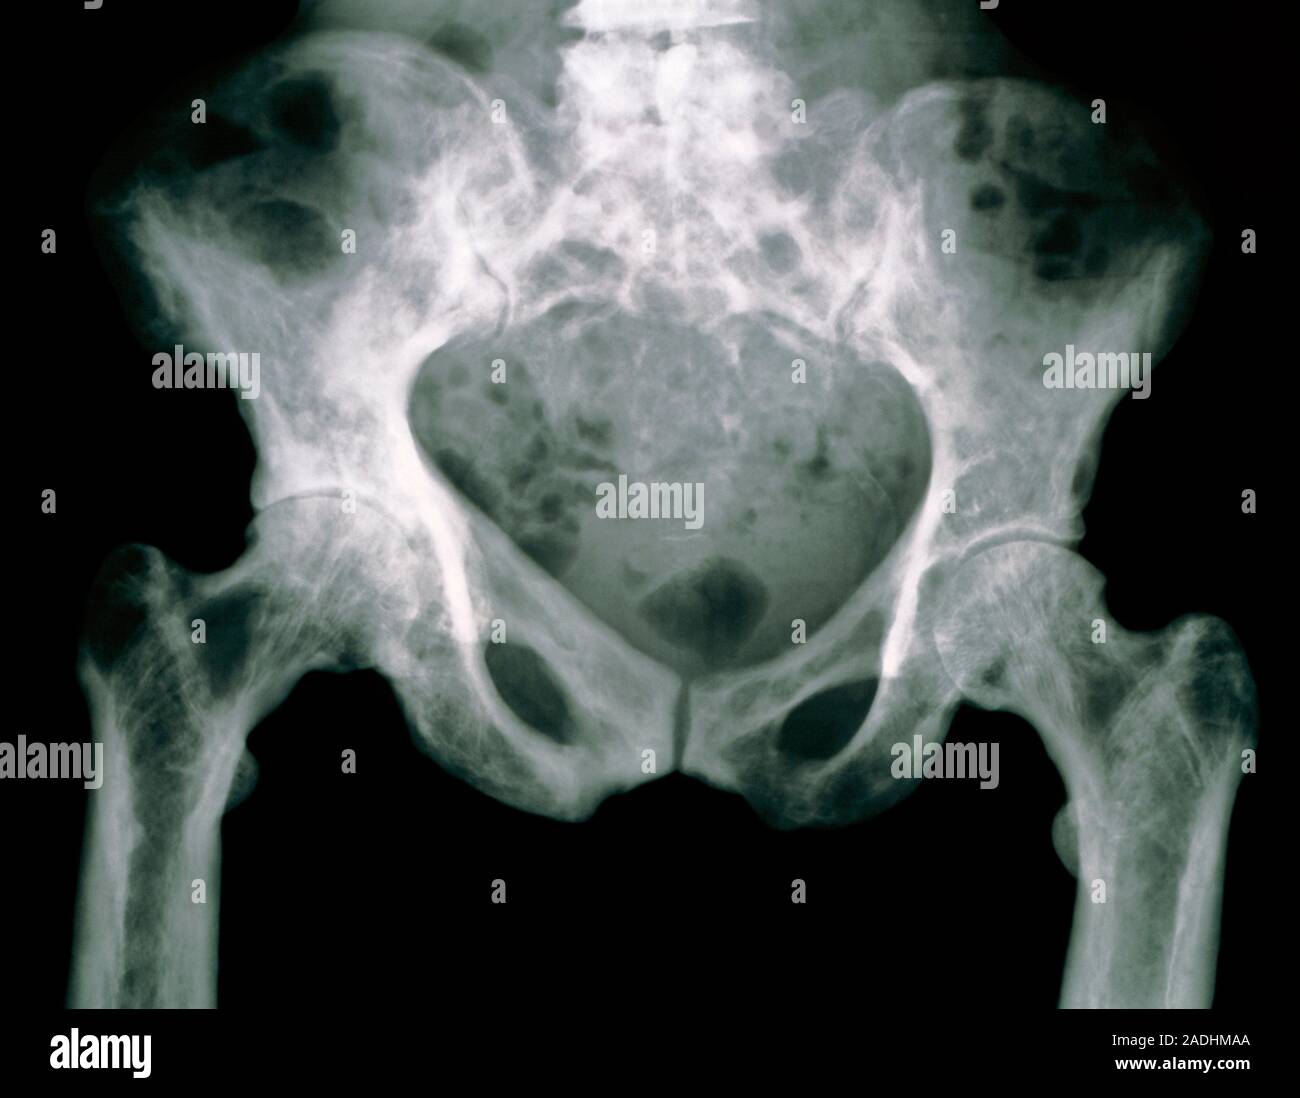

From www.alamy.com

Paget's disease. Coloured Xray showing the pelvis of a person Paget's Disease Left Hip Icd 10 They also might break easily. Paget's disease of bone causes your bones to grow larger and weaker than normal. Paget disease is a skeletal growth disorder in which abnormalities such as unusual bone growth can occur in. A chronic condition in which both the breakdown and regrowth of bone are increased. M88.88 is a billable diagnosis code used to specify. Paget's Disease Left Hip Icd 10.